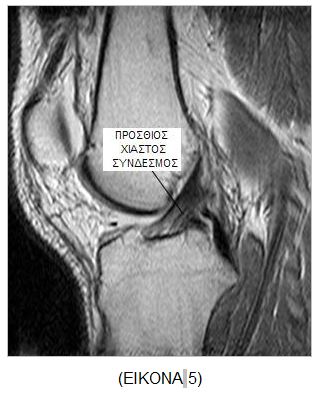

MAΓΝΗΤΙΚΗ ΤΟΜΟΓΡΑΦΙΑ25 (ΕΙKONA 5)

Ο Π.Χ.Σ. αξιολογείται καλύτερα στις οβελιαίες τομές με το γόνατο σε 100 – 150 έξω στροφή και πλήρη έκταση. Απεικονίζεται ως σκοτεινή δέσμη με χαμηλό σήμα στις Τ1 ακολουθία. Στις οξείες ρήξεις ο σύνδεσμος είναι ασαφής ή ελικοειδής με κοίλο πρόσθιο χείλος. Η γωνίωση του οπίσθιου χιαστού υποδεικνύει την πλήρη ρήξη του Π.Χ.Σ. Σύμφωνα με τον Minck36 η μέθοδος εμφανίζειn ακρίβεια 95 % στην ανίχνευση ρήξεων του συνδέσμου οι οποίες επιβεβαιώθηκαν αρθροσκοπικά.

Αν προστεθεί και η Τ2 ακολουθία η ακρίβεια της μεθόδου αυξάνεται σε 97 %. Η ευαισθησία της μεθόδου ανέρχεται σε 93 % κατά τον Fischer37. Ιδιαίτερα επιβοηθητικά για τη διάγνωση των ρήξεων του Π.Χ.Σ. είναι τα έμμεσα ευρήματα όπως η αύξηση της κυρτότητας του οπίσθιου χιαστού και οιοστικές θλάσεις στον οπίσθιο έξω μηριαίο κόνδυλο. Η ειδικότητα των έμμεσων αυτών ευρημάτωνανέρχεται σε 91 - 100 %, η ευαισθησία όμως καταγράφεται ίση με 19 - 90 %38.